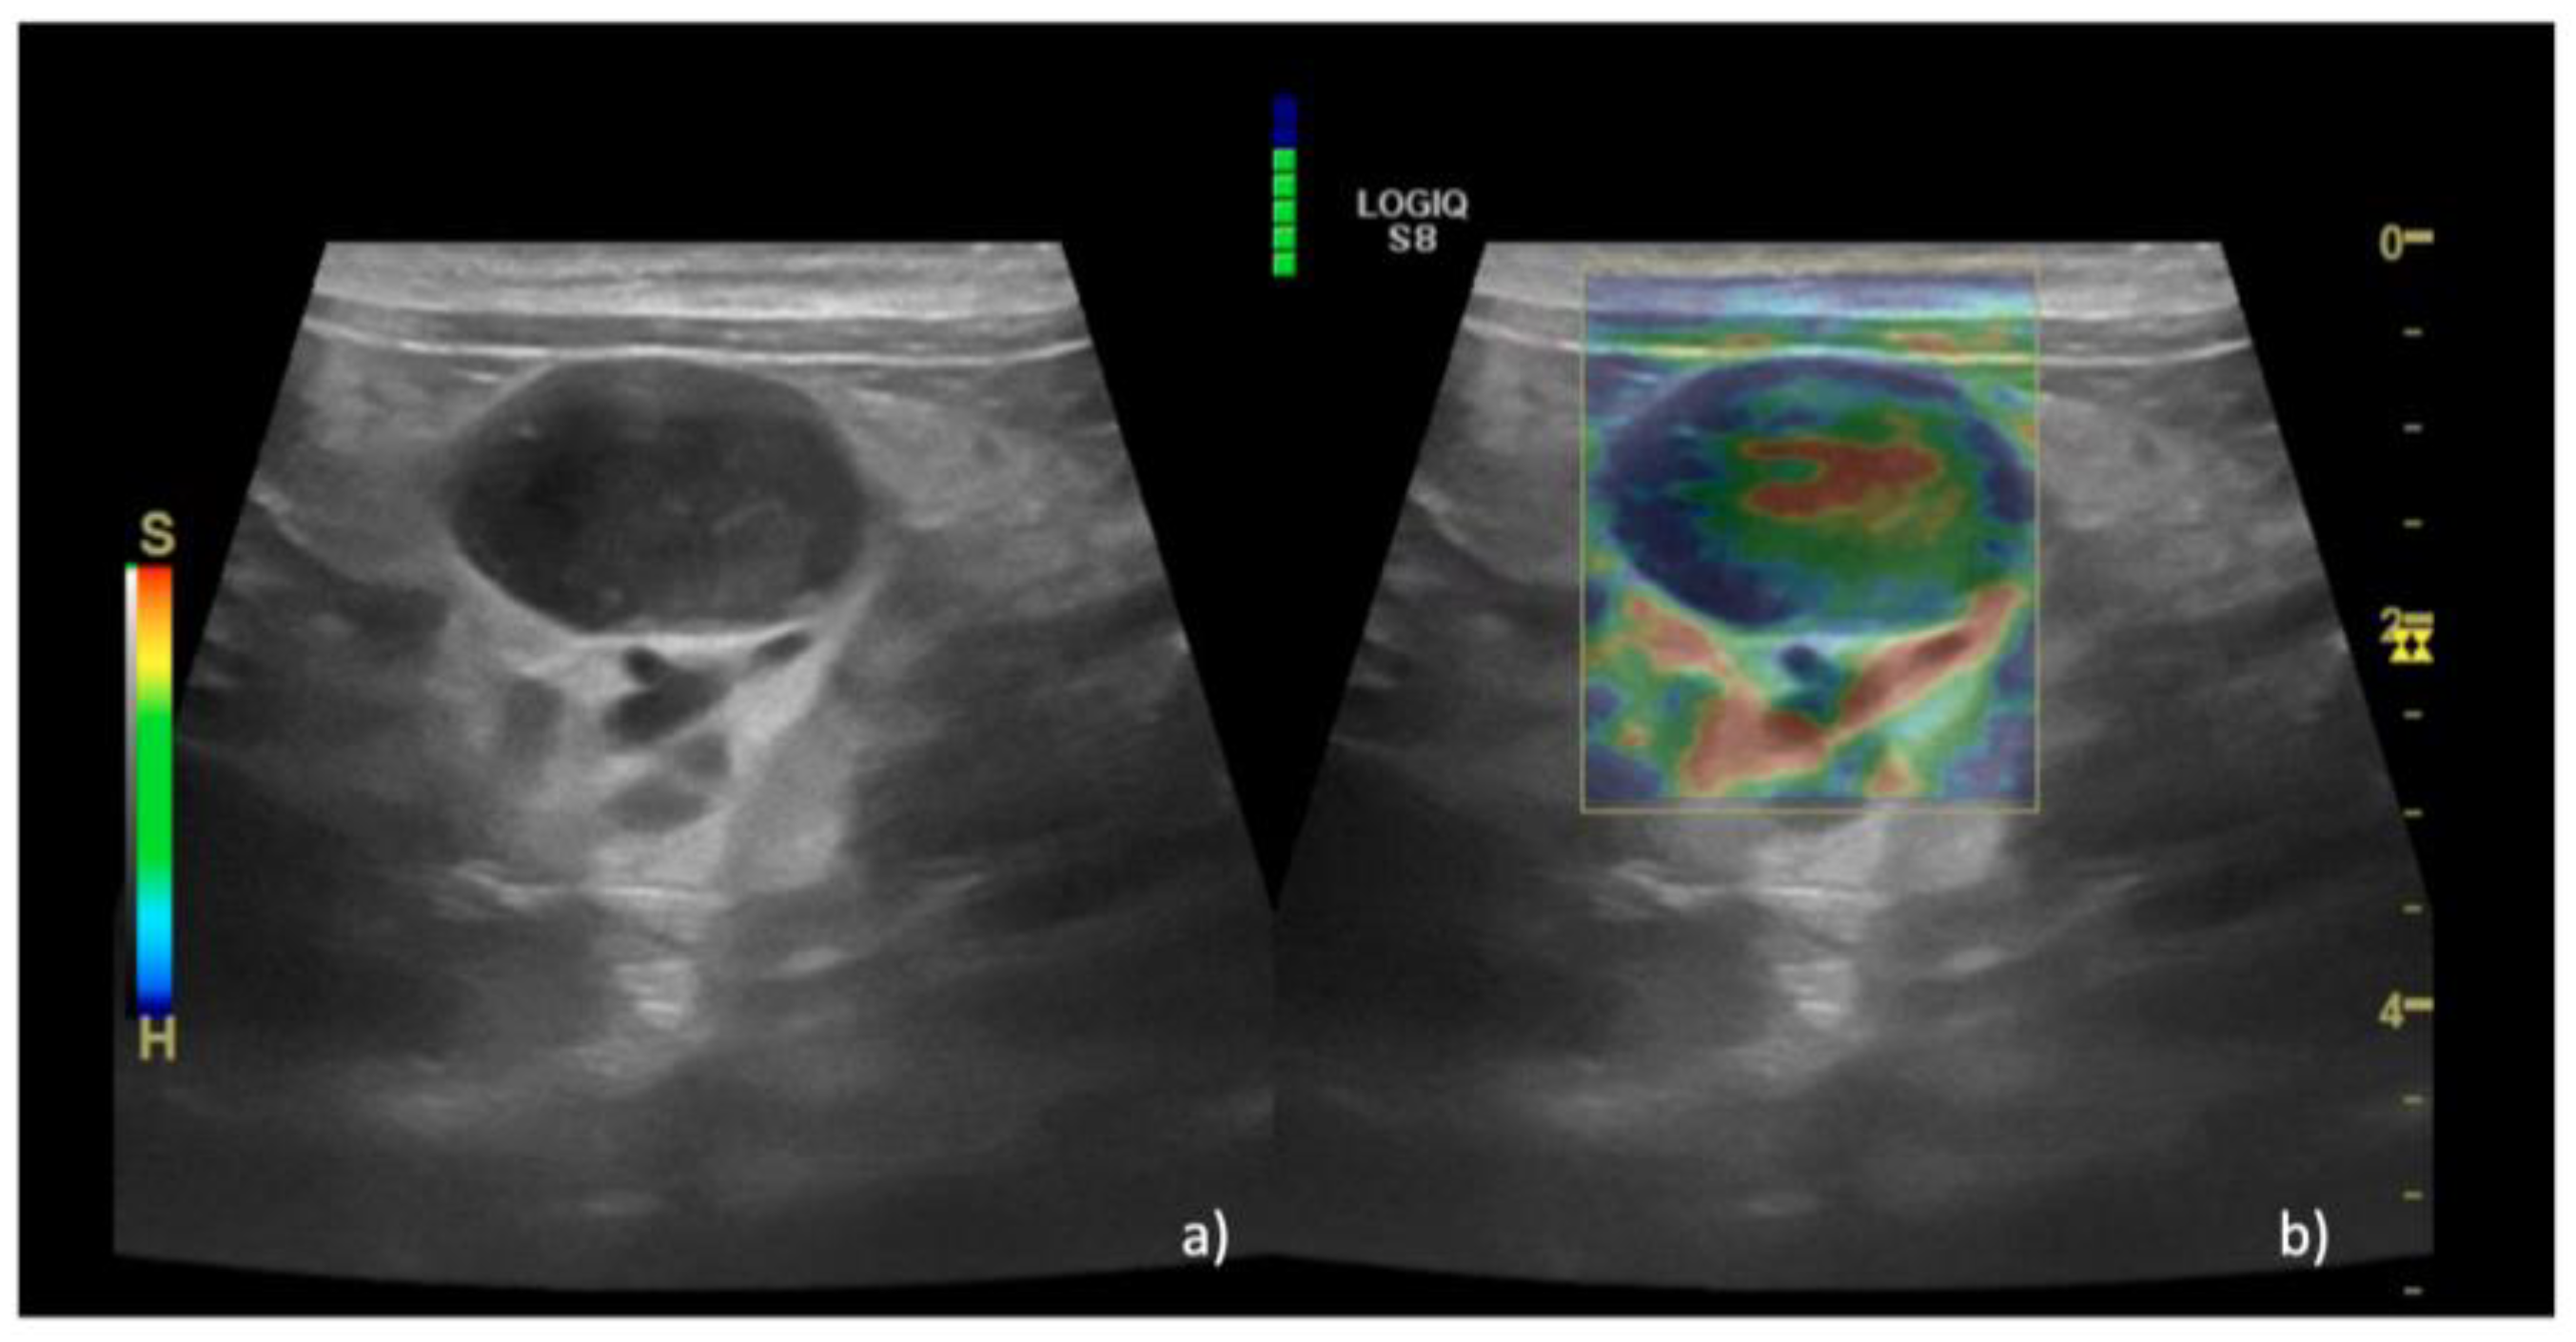

3. Results

| Sonoelastography | ||||

| EP | 1 n = 15 (36%) | 1 n = 0 | 1 n = 0 | |

| 2 n = 14 (35%) | 2 n = 0 | 2 n = 2 (4%) | ||

| 3 n = 11 (29%) | 3 n = 0 | 3 n = 15 (36%) | ||

| 4 n = 0 | 4 n = 0 | 4 n = 24 (58%) | ||

| 5 n = 0 | 5 n = 6 (100%) | 5 n = 1 (2%) | ||

| Median (IQR) | 2 (1–3) | 5 (5–5) | 4 (2–5) | 0.01 |

| SR, Median (IQR) | 0.5 (0.1–0.9) | 1.8 (1.5-2.2) | 0.7 (0.1–1.6) | 0.01 |